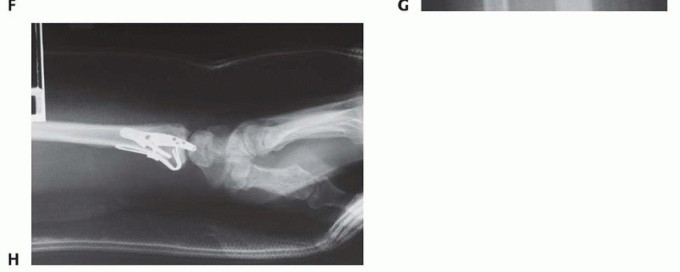

TECH FIG 6 • Volar rim fixation with a volar buttress pin. A,B. Articular fracture with axial instability pattern of volar rim. C. Insertion of Kirschner wires. D. Cutting and inserting legs. E. Reduction of teardrop.(continued)

TECH FIG 6 •(continued)F. Completed fixation. G,H. Volar buttress pin fixation to control rotational alignment of volar rim fragment. Fine-tune the reduction and fix it proximally with a minimum of two screws and washers ( TECH FIG 6F-H). If needed, a blocking screw can be placed just proximal to the end of the buttress pin to prevent shortening of the fragment. Alternatively, a wire plate can be used to secure the implant proximally.